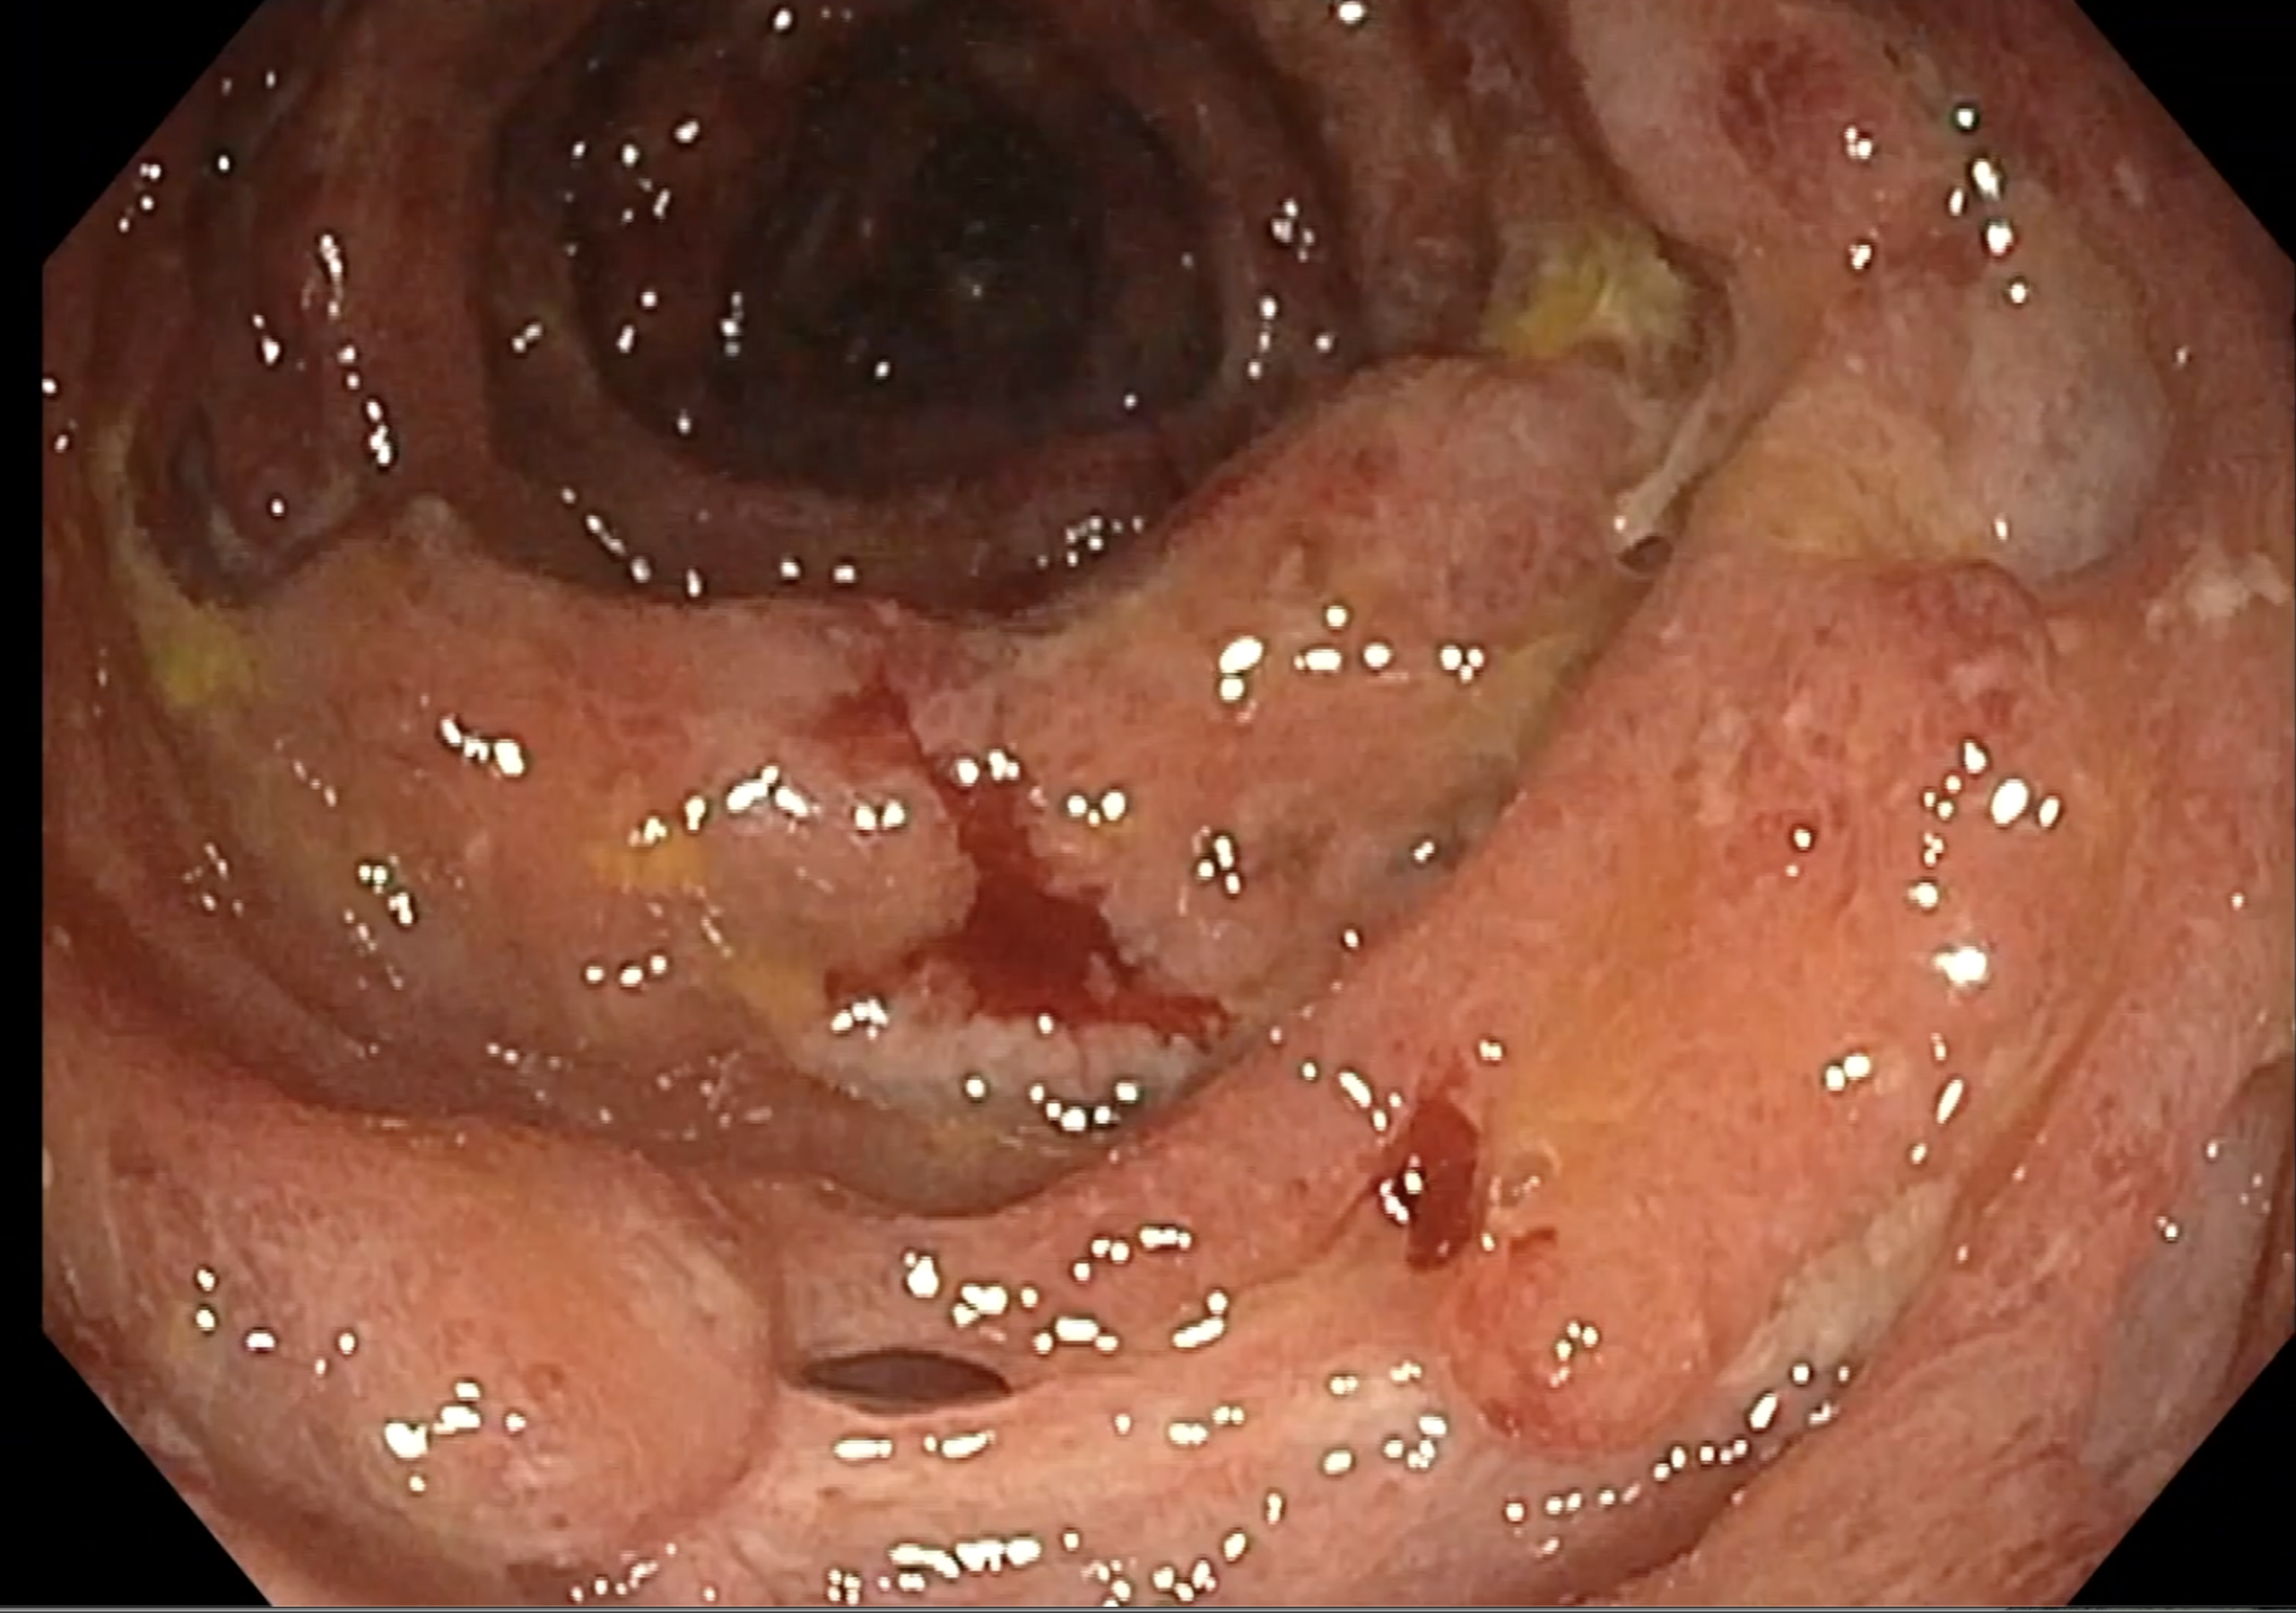

Coloscopie: Mayo 3 UCEIS 7/8

Histologie : rectocolite hémorragique sans surinfection à CMV

Là encore la paroi est très hypoéchogène, la structure en couches est par endroit totalement absente, ulcérations en surface, infiltration de la graisse, doppler intense, petites adénopathies périphériques.

Le rectum est bien vu avec la sonde basse fréquence la paroi atteint 10 mm à ce niveau.

Le score de Milan MUC est de (10 x1,4+2) = 16